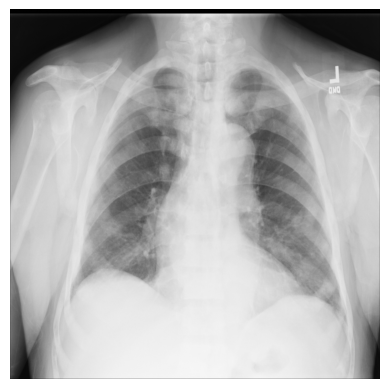

Examine an X-ray with imageio¶

Let’s begin with a simple example using just one X-ray image from the ChestX-ray8 dataset.

The file — 00000011_001.png — has been downloaded for you and saved in the

/tutorial-x-ray-image-processing folder.

1. Load the image with imageio:

3. Import matplotlib and display the image in a grayscale colormap:

import matplotlib.pyplot as plt

plt.imshow(xray_image, cmap="gray")

plt.axis("off")

plt.show()